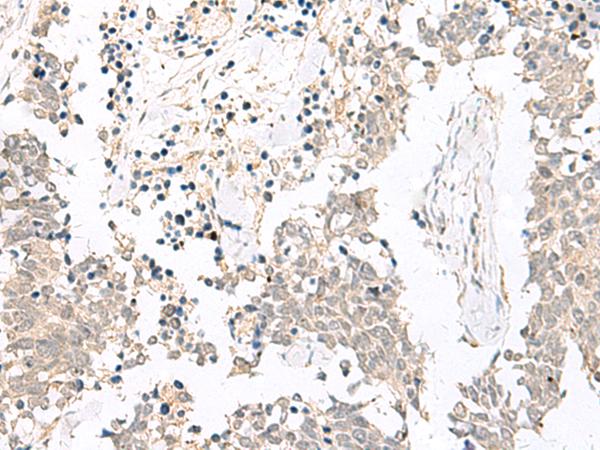

IHC positive control:

Human lung cancer and Human esophagus cancer

IHC Recommend dilution:

20-100